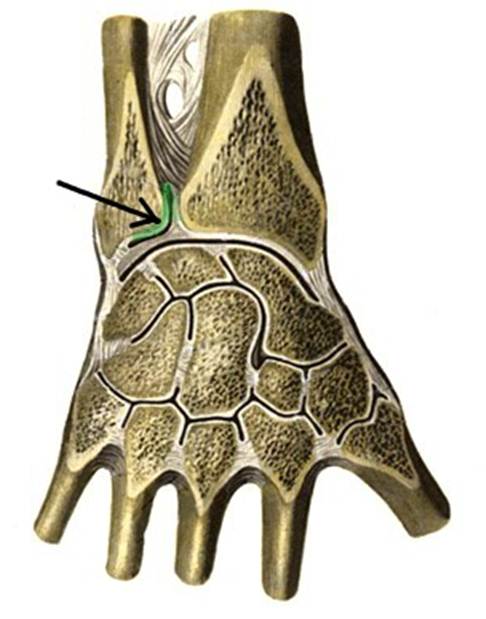

I:

I:

I:

I:

I:

I: